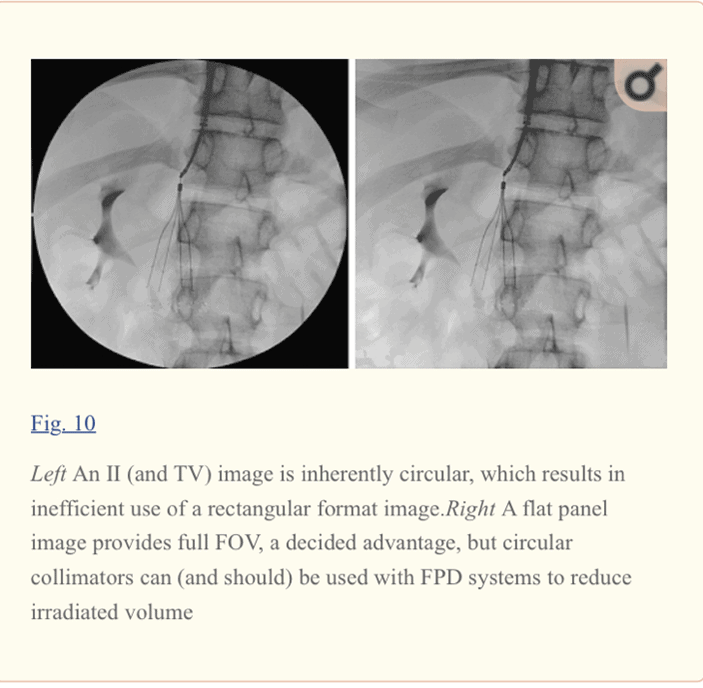

The FPD provides 100% usable field of view than the image intensifier.